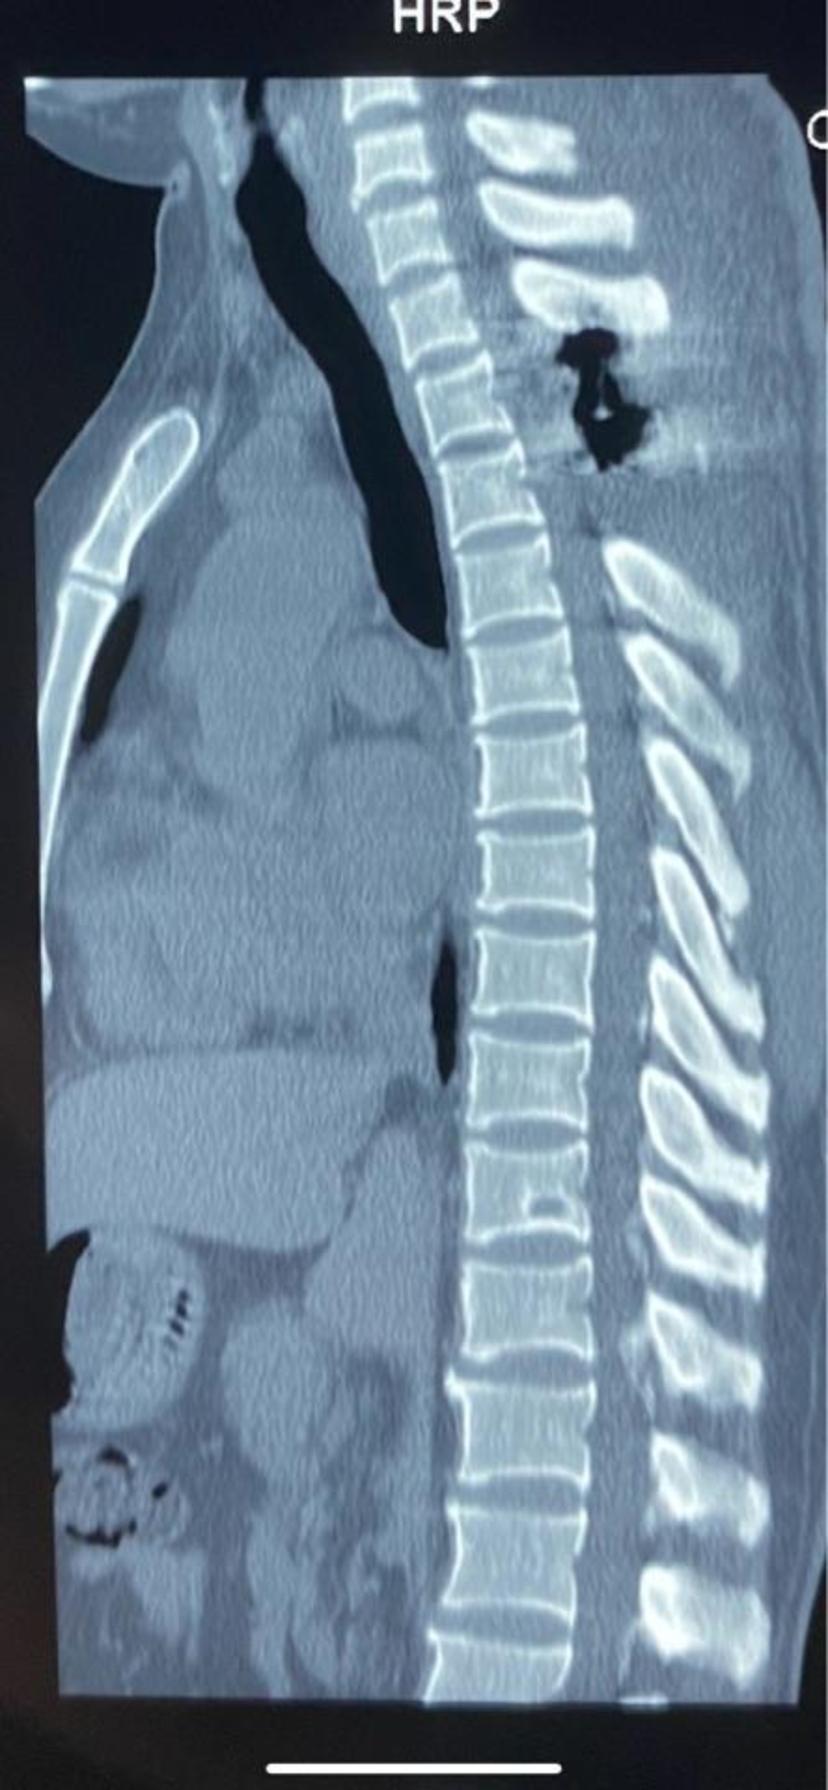

患者出现胸背部束带感、双下肢无力、行走困难两年余,因位置较高,胸2-3平面严重黄韧带骨化,继发椎管狭窄,因手术风险极大,多地求医未果,行后路彻底减压后,术后一周恢复良好,康复出院,感谢您的锦旗对我工作的认可!胸椎磁共振显示胸2-3平面黄韧带骨化物压迫脊髓

CT显示骨化物占满整个椎管,脊髓严重受压